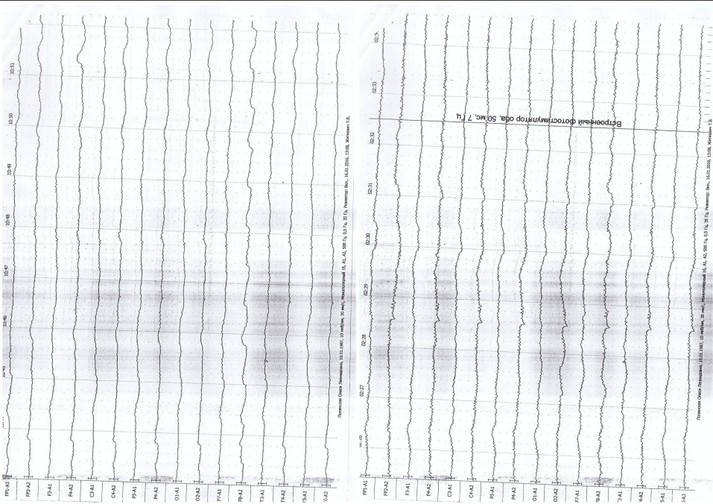

«Ми всі віримо, що одного разу Олеся повернеться до життя. Незважаючи на те, що вона в комі, у неї добрі аналізи, організм функціонує. Вона чує, коли до неї говорять, реагує на звуки. Коли до неї підходять близькі або підносять сина, вона повертає голову. Звичайно, вона не може бачити. Лікарі з Чернігова сказали, що пошкоджено очний нерв. Але, очевидно, вона щось відчуває», – розповіла Ткаченко.